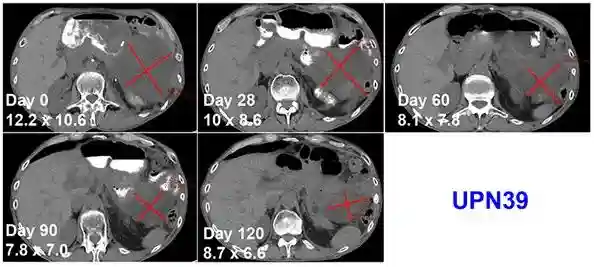

在治疗安全性得到保证的同时,患者们也有一些临床表现方面的改善,其中2人疾病稳定,另外1人出现了混合性反应,他的腹部肿块在4个月里持续缩小,在第4个月时仅有原来的50%左右,但其他病变同时发生了进展。

患者的肿瘤缩小情况(红色为肿瘤区域)